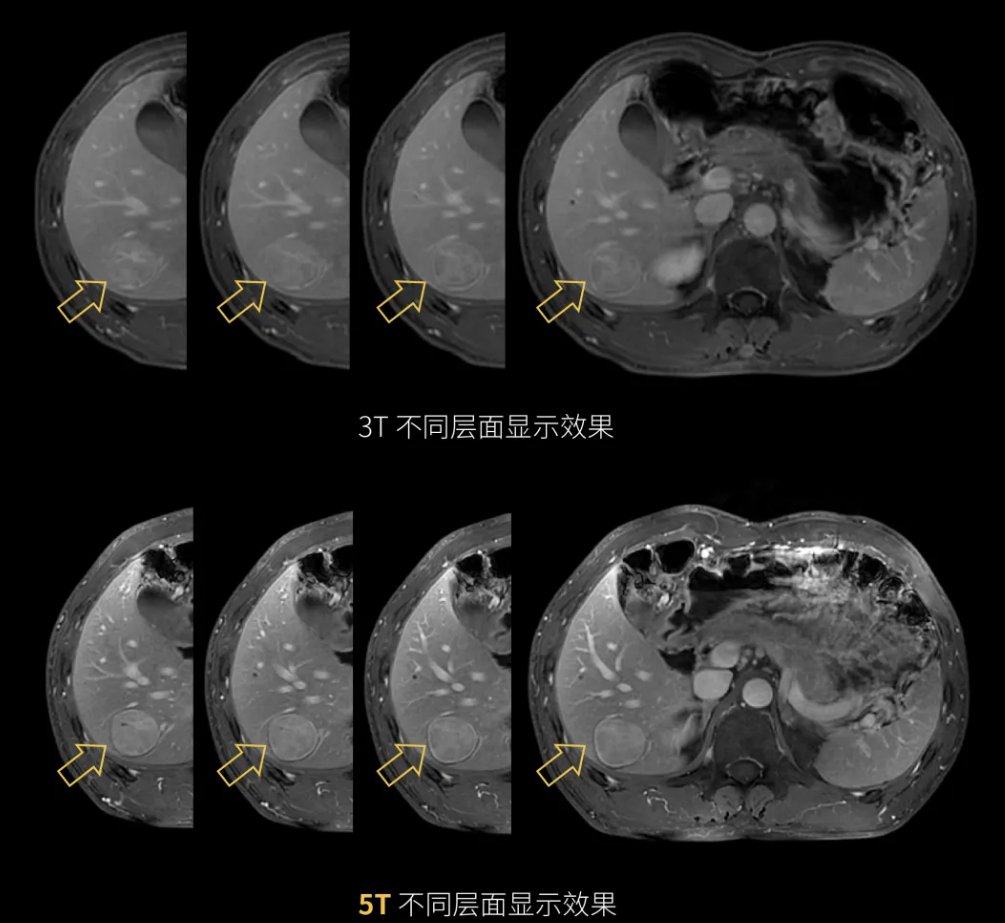

5T超高分辨腹部成像

超高分辨腹部成像

3T和5T不同层面显示效果